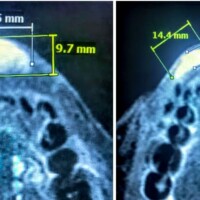

Diagnosis is made by ultrasound, MRI, and rarely CT scans depending on location and pattern of presentation. Most commonly, the first-line treatment is drainage of the cysts by a catheter followed by injection of the drained cyst cavity with a sclerosant (a detergent-like compound that causes irritation, inflammation, and gradual collapse of lymphatic cyst). This is most successful for larger cysts (those greater than 2 cm). Smaller cysts, called microcysts, are more difficult to treat. Multiple treatment sessions may be required, and recurrence is not uncommon.